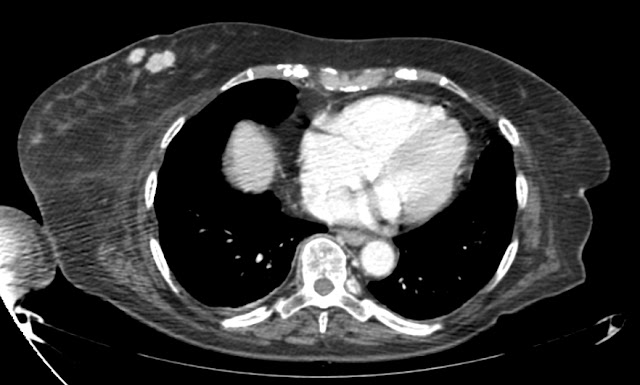

Angiotomografía (ATAC), dependen del tiempo y disponibilidad que tengamos de radiólogo. Normalmente se hace después de haber hecho la ecografía y si se hace urgente suele ser por indicación del mismo radiólo en ese momento (al menos en nuestro centro, que es un centro comarcal que no puede andarse con estos lujos de forma habitual)